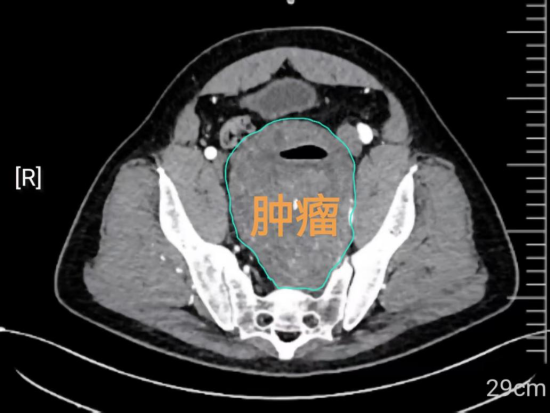

两位专家通过远程会诊,多次研判张先生的影像资料,发现肿瘤体积巨大、位置深在,最大径线达12.5厘米,且隐匿于盆腔深部的腹膜后间隙。该区域解剖结构复杂、空间狭窄,密布大血管、神经丛及重要脏器,手术显露极为困难。患者有高血压病史12年、脑血管狭窄2年,这对麻醉管理与术中血压平稳控制提出了更高要求。同时,其右肾积水、左肾萎缩,肾功能已濒临不全边缘。手术必须确保右侧输尿管通畅,保护唯一有功能的右肾,避免术后肾衰竭的发生。